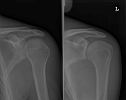

Schouder - Bovenarm

Schouder |